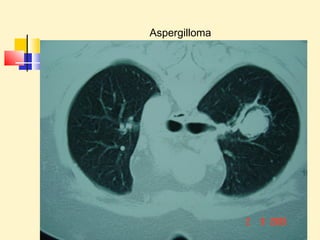

Aspergilloma

Aspergiloma ( Hemoptysis)